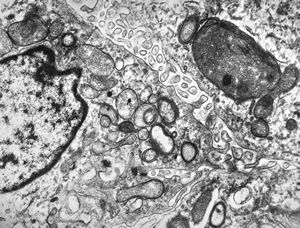

M,3y. | globoid leukodystrophy of Krabbe - n.suralis

M,3y. | globoid leukodystrophy of Krabbe - n.suralis

M,3y. | globoid leukodystrophy of Krabbe - n.suralis

M,3y. | globoid leukodystrophy of Krabbe - n.suralis

M,3y. | globoid leukodystrophy of Krabbe - n.suralis